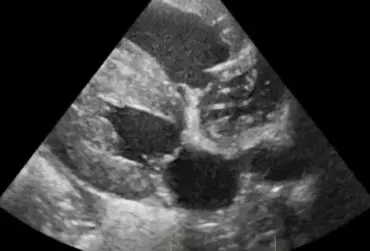

Echo serca z widoczną obecnością dużej liczby nicieni w prawym przedsionku serca (4)

16 kwietnia 2019

Wojciech Atamaniuk

Czytaj więcej